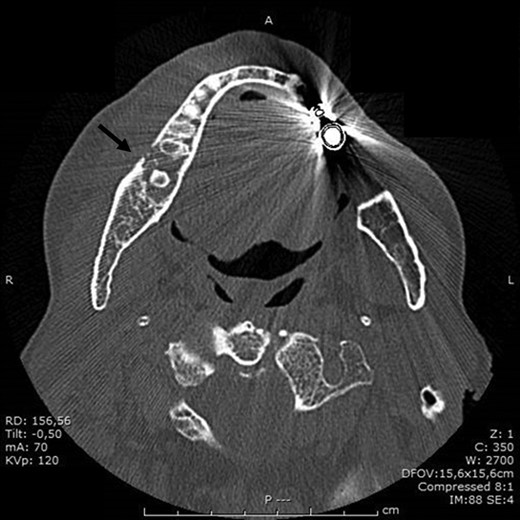

BRONJ was clinically diagnosed at the patient’s first visit based on her history and was confirmed radiologically by the dental x-ray and CT performed in July 2016. X-rays showed reduced density of the alveolar bone edges, particularly on the right where the alveolar bone crest profile was rather irregular. A small residual root was present in the molar region on the right. The inferior alveolar nerve canal was clearly recognizable, on both sides.

In the light of these results, it was decided in September 2016 that the patient should undergo major surgery involving mandibular bone curettage and positioning of HAM (Fig. 1).

In November 2016, the patient underwent surgery under general anaesthesia. After infiltration of a local anaesthetic (mepivacaine + adrenaline 1:200 000), surgery was carried out as described: mucoperiosteal incision of the right mandible with mesial and distal drainage, extensive fistulectomy of the hyperplastic mucose membrane, which showed multiple fistulas, skeletonisation and exposure of abundant necrotic tissue; debridement of hyperplastic-inflammatory tissue and ostectomy of necrotic bone with osteoplasty of sharp edges; positioning of HAM and water and hermetic suture with Polisorb 3/0 absorbable braided thread (Fig. 2A–E). Histological examination confirmed the presence of inflammation and the diagnosis of osteonecrosis. The mesial and distal bone curettage margins were dictated by the x-ray images (Fig. 3) identifying above all the radio-opaque areas, often associated with a periosteal reaction, as well as by the need to remove any bone sequestra present. The imaging was also associated with the intraoperative assessment of the macroscopic appearance of the bone and in particular the signs of bleeding from the cortex and medulla. The HAM was 3 × 3 cm2 in size and was positioned over the curetted area and under the mucosal flap.

In November 2016 the patient underwent surgery under general anaesthesia (same technique used for the first patient described) (Fig. 4A–D). The mesial and distal bone curettage margins were dictated by the x-ray images (Fig. 5) which identified above all the radio-opaque areas, often associated with a periosteal reaction, as well as by the need to remove any bone sequestra present. The HAM was 3 × 3 cm2 in size and was positioned over the curetted area and under the mucosal flap.